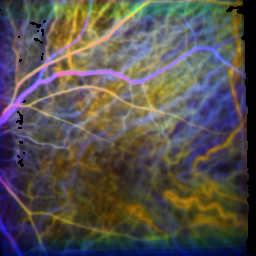

Three of these four parameters were visualized in the color image representation — representing the influx behaviour information. Warm colors (red, orange, yellow) indicate

that the flooding early/fast was, cold colors (turquoise, blue) that it was late/slow, colorless from a time-average influx behaviour.

On this page, the colors in the images are normalized in each case to its own averaged influx behaviour, so the colors visualize for time differences within the means of recording.

Control participant

time of the maximum: 26.5 f ± 19.6%visual acuity: 1.00